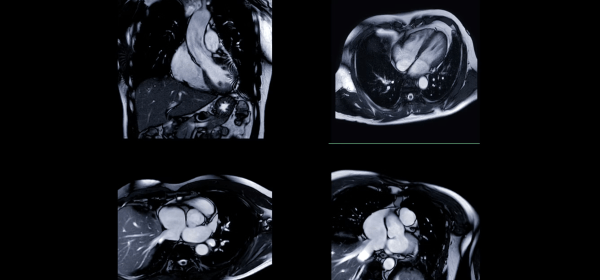

AI can guess racial categories from heart scans – what it means and why it matters

UK: How “AI” Imports “Racism” into Medical Heart Scans! (10.1.2026)

In the heart scan study, researchers found that the AI model wasn’t actually focusing on the heart itself, where there were few visible differences linked to racial categories. Instead, it drew information from areas outside the heart, such as subcutaneous fat as well as image artefacts – unwanted distortions like motion blur, noise, or compression that can degrade image quality. These artefacts often come from the scanner and can influence how the AI interprets the scan.